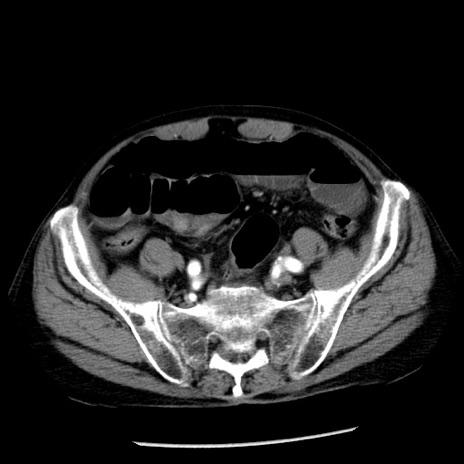

冠状断像

【症例】80歳代男性

【主訴】嘔吐

【現病歴】昨晩2回嘔吐あり、今朝になっても嘔吐あり。来院。

【既往歴】胃潰瘍

【身体所見】意識清明、BT 37.6℃、BP 166/95mmHg、HR 100bpm、SpO2 97%、腹部:平坦・軟、腸蠕動音聴取良好、圧痛なし。

【データ】WBC 21900、CRP 1.46